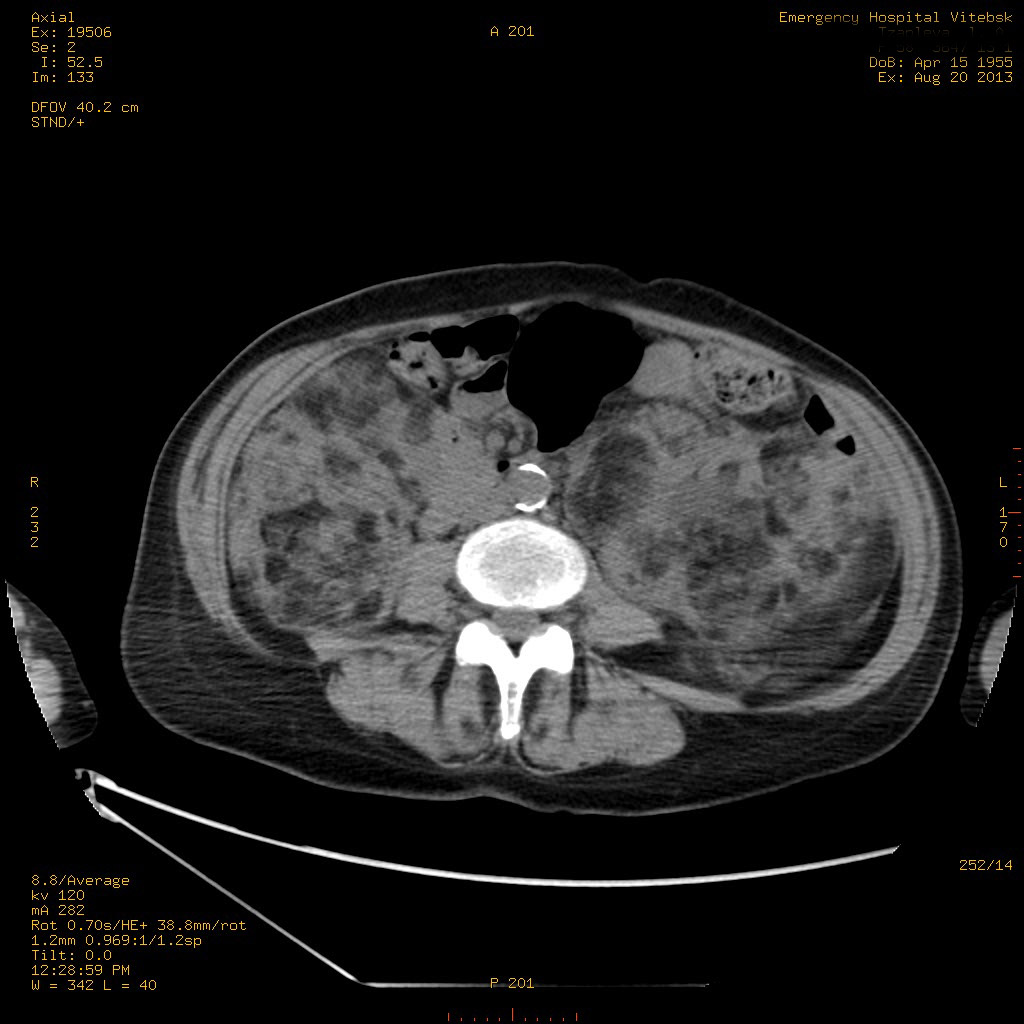

Пожилая женщина с нормальными мочевиной и креатинином.

Ангиомиолипоматоз почек , думаю компонент туберозного склероза.

Да, туберозный склероз.

Случай консультирован на кафедре радиологии Католического университета г.Лёвен (Бельгия) - зав каф. профессор Р.Оуен.